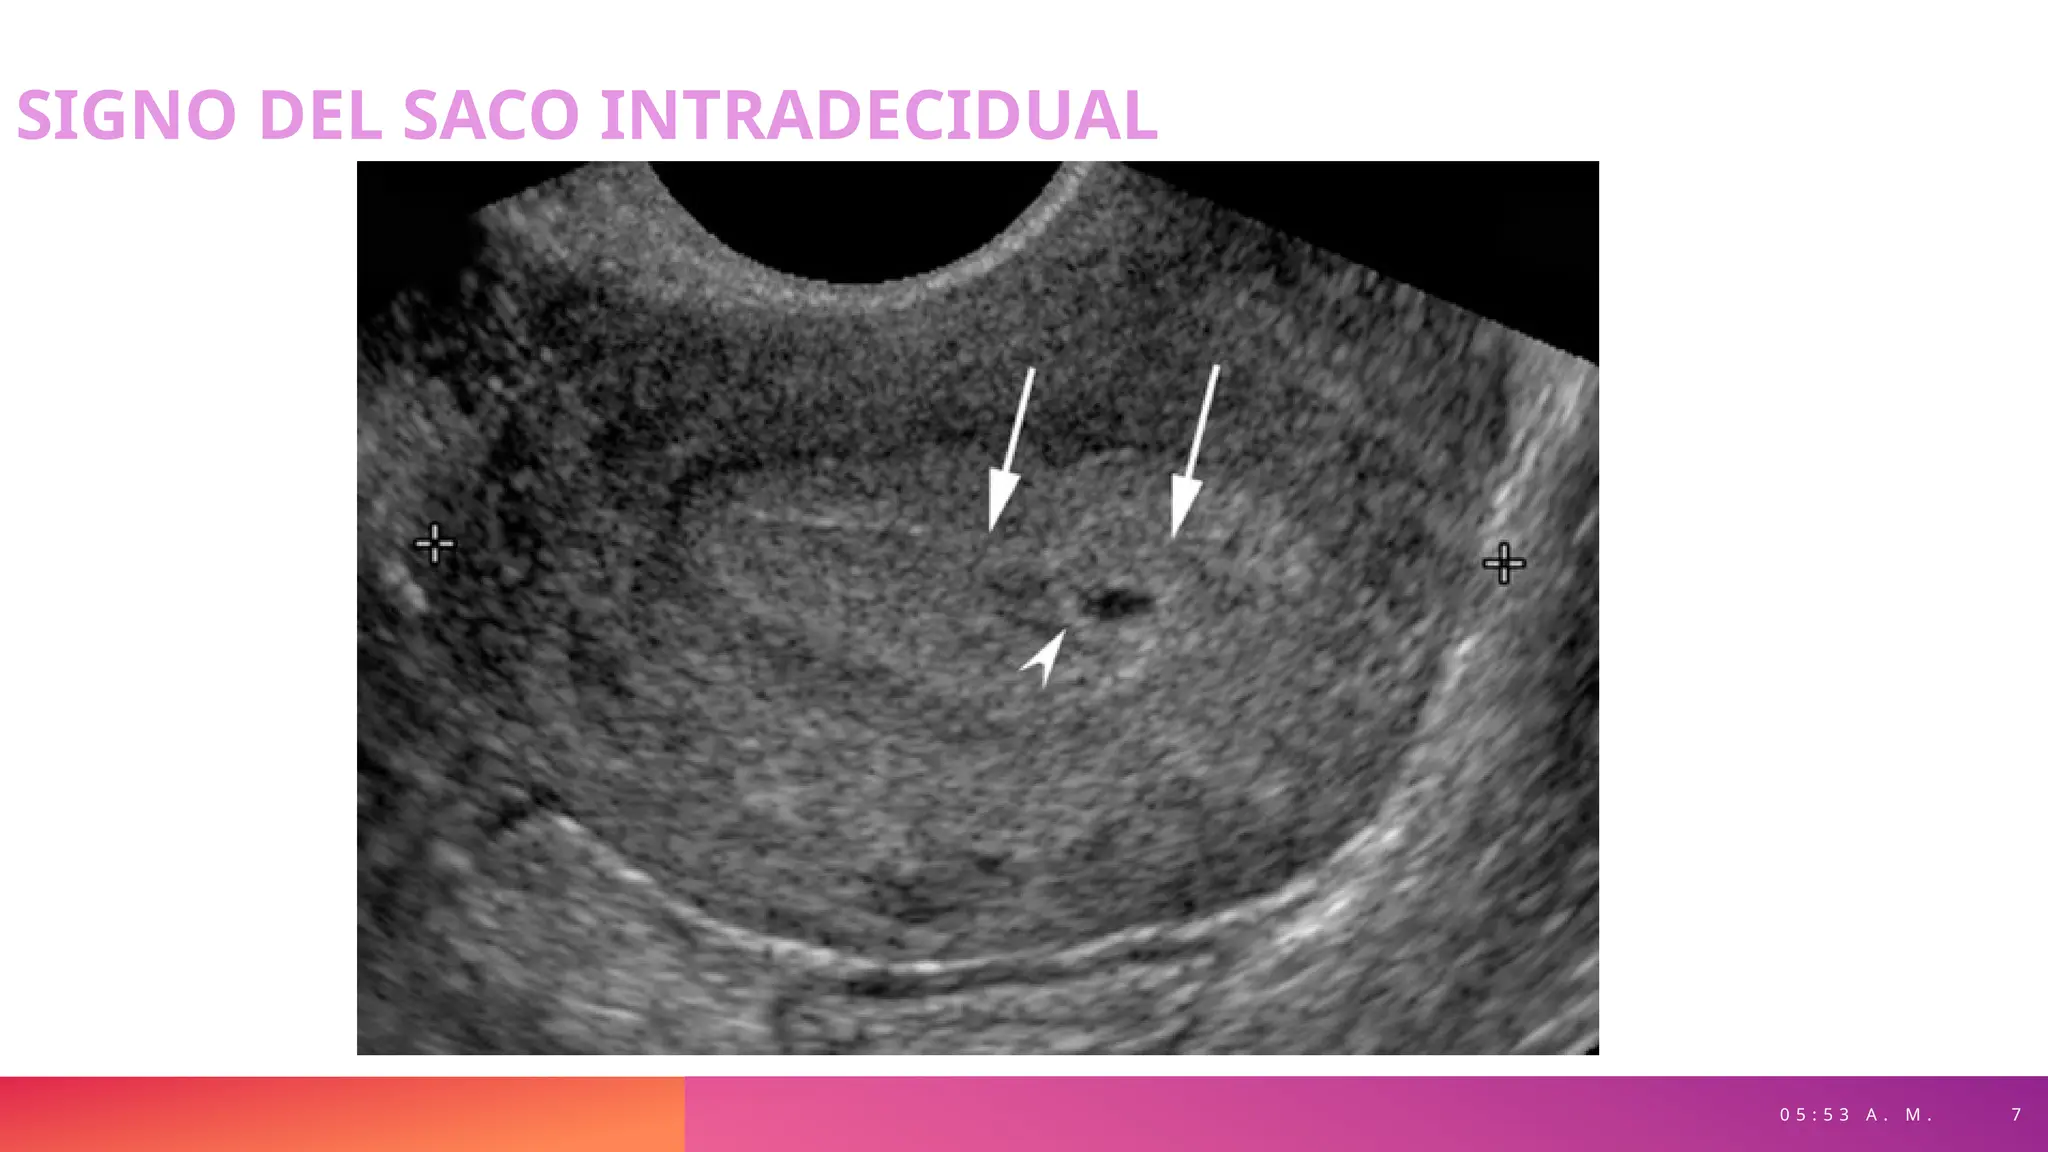

SIGNO DEL SACO INTRADECIDUAL

0 5 : 5 3 A . M . 7

• Colección de líquido, uniforme y

redondeada dentro de la

cavidad uterina

• Localización normalmente en la

porción media-superior de la

• Rodeada por un anillo

hiperecogénico

• Visible aproximadamente en la

4ª. Semana de gestación